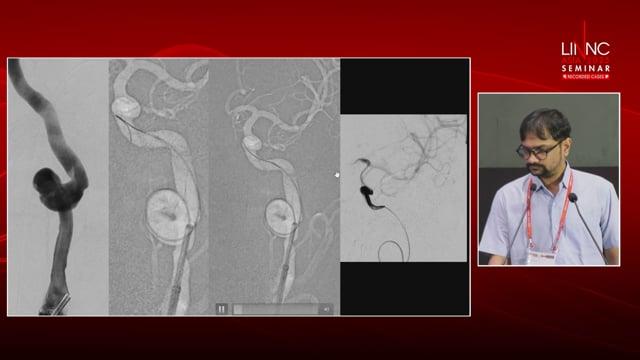

«Catch» the displacement of the WEB!

AneurysmsIntrasacular devices

May 28, 2025